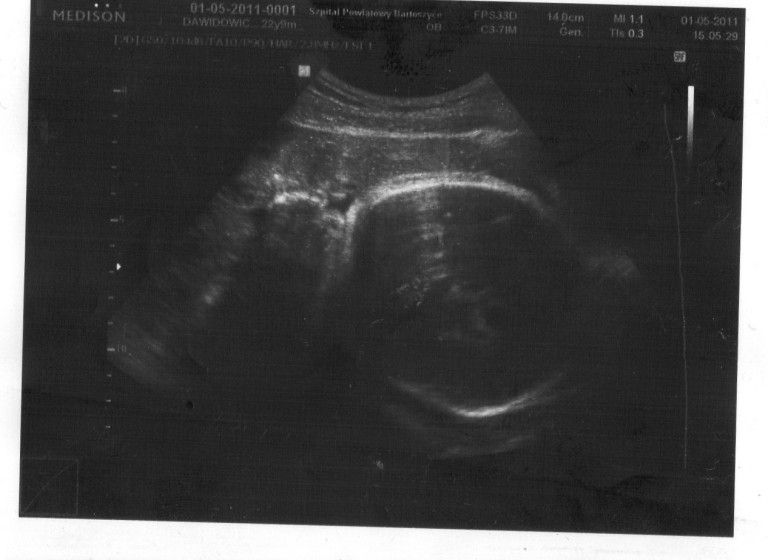

. Jak poszłam na wizytę do doktora cała się trzęsłam, powiedziałam mu o swoich obawach. Pan doktor na szczęście mnie uspokoił, zrobił usg i jak tylko zobaczyłam moją "fasolkę" na monitorze poczułam, że czeka mnie coś nowego, wspaniałego. Było to uczucie nie do opisania:-) Odetchnęłam, wróciłam do domku, zaczęłam rozmyślać o dziecku i w końcu się zarejestrowałam na familie